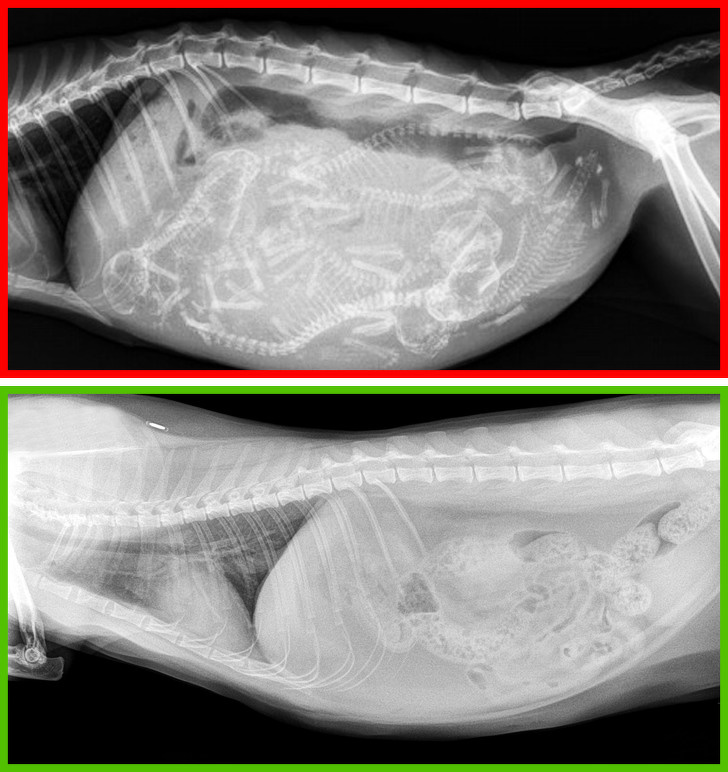

1. Відмовлятися від кастрації та стерилізації

Вгорі — рентгенівський знімок вагітної кішки, внизу — кастрованого кота.

Ці процедури у більшості випадків позитивно впливають на організм домашніх тварин. У кішок знижується ризик виникнення раку молочної залози, а у котів — раку яєчок. Крім того, кастровані коти рідше тікають з дому і проявляють агресію.